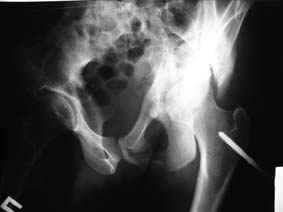

Все-таки надо бы начать не с КТ, а с обзорного снимка таза и косых проекций впадины.

Это обзорные и косые снимки